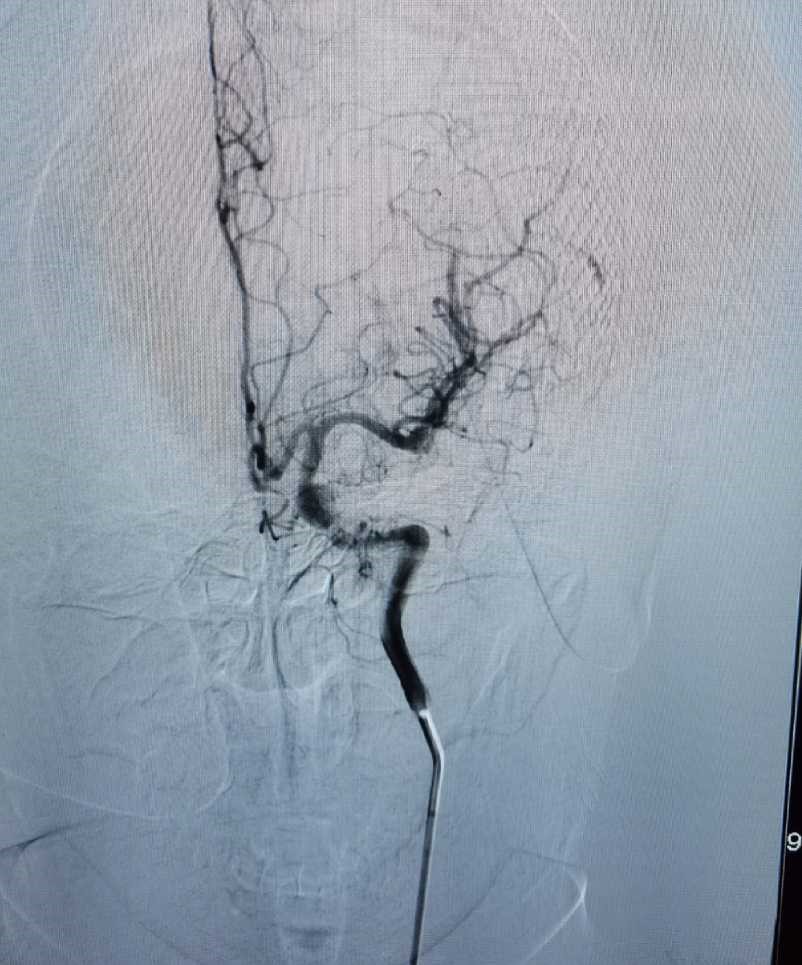

后患者无明显并发症出现,恢复良好。行DSA检查:见畸形血管团消失。